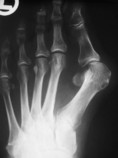

Hallux valgus

Der Hallux valgus ist eine klassische Zivilisationskrankheit. Frauen sind deutlich häufiger betroffen als Männer. Es wurden in der Geschichte der Vorfußchirurgie eine Vielzahl an verschiedenen OP-Verfahren beschrieben. Insgesamt über 200 verschiedene Methoden. Die meisten dieser Therapieansätze konnten sich jedoch aufgrund mannigfaltiger Nachteile nicht halten.

Die Entscheidung über das geeignete OP-Verfahren zur Therapie des Hallux valgus hängt von dessen Stadium ab. Dieses wird anhand der klinischen Untersuchung und der Röntgendiagnostik festgelegt.